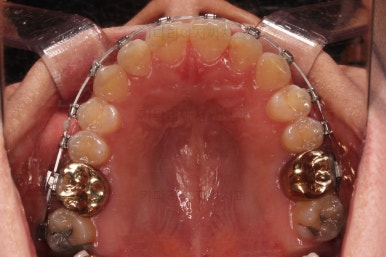

수술 후에 오셨어요.

적절한 교정치료로 수술 후 교합을 맞추는 과정을 거쳐야 했고요.

적절한 마무리 후에 부산안면비대칭 교정치료도 종료하게 됩니다.

중앙선에는 비대칭이 남았죠?

애초에 수술을 전제로한 교정치료를 시작했었다면 충분히 더 개선될 수 있는 부분이었는데요.

중간에 치료 방향을 바꾸었던터라 중앙선까지는 맞추기 힘들다는 점을 환자분도 인지하시고 들어가셨어요.

그래도 기능적으로 문제 없었고, 가지런한 느낌 좋아서 부담 없이 마무리를 할 수 있었습니다.